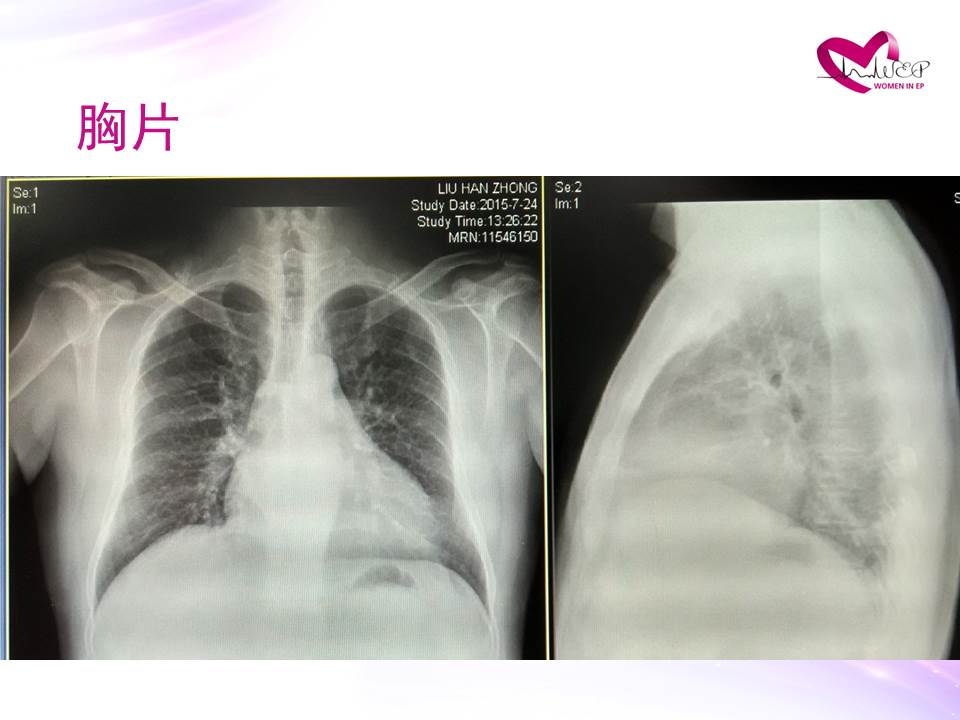

META病例|戴研:VVI升级至CRTD报告